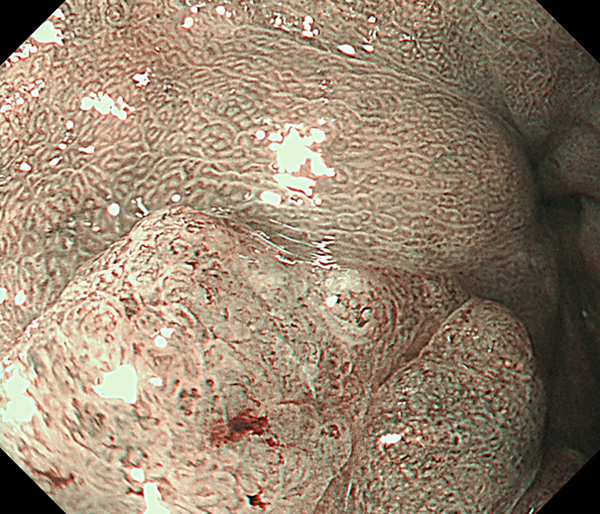

内視鏡所見と病理組織像の1対1対応が可能な症例を公募いたします。主にLSBEに発生した早期癌(HGDを含む)を対象としますが、興味深い症例であればSSBE癌でも結構です。採否は世話人へご一任ください。

症例呈示希望者は応募用紙に記入の上、代表的な内視鏡(2枚)、切除標本(新鮮、固定)、切り出し図、マッピング、代表的組織像とともに、Barrett 食道研究会事務局 barrett.shinshu@gmail.comへお申し込み下さい(10MB以下でお願い致します)。

特に、本邦では極めて稀なlong segment Barrett’s esophagus(LSBE)から発生した早期癌は、診断に難渋する場合も多く、欧米ではランダム生検による検出が標準的とされています。背景のBarrett食道もろとも全体を内視鏡切除+ラジオ波焼灼する欧米と異なり、ESDで内視鏡的な局所切除が基本の本邦では、存在診断+範囲診断(特に水平)を的確に行うことが不可欠です。

そのためには、一流の病理医による組織学的診断とエキスパート内視鏡医による拡大内視鏡像との一対一対応を徹底的に行うことで、『本来、見えないであろう拡大所見の先にある組織構築像が診えてくる』所まで内視鏡診断レベルを上げていく必要があります。その実現には、一対一対応を追究した症例(特にLSBE発生例)1例でも多く経験するしかありません。本研究会でBarrett食道腺癌(LSBE発生早期病変)を共に学び、拡大内視鏡像の一歩先を診るスキルを習得しましょう!一人でも多くの皆様のご参加をお待ちしています。